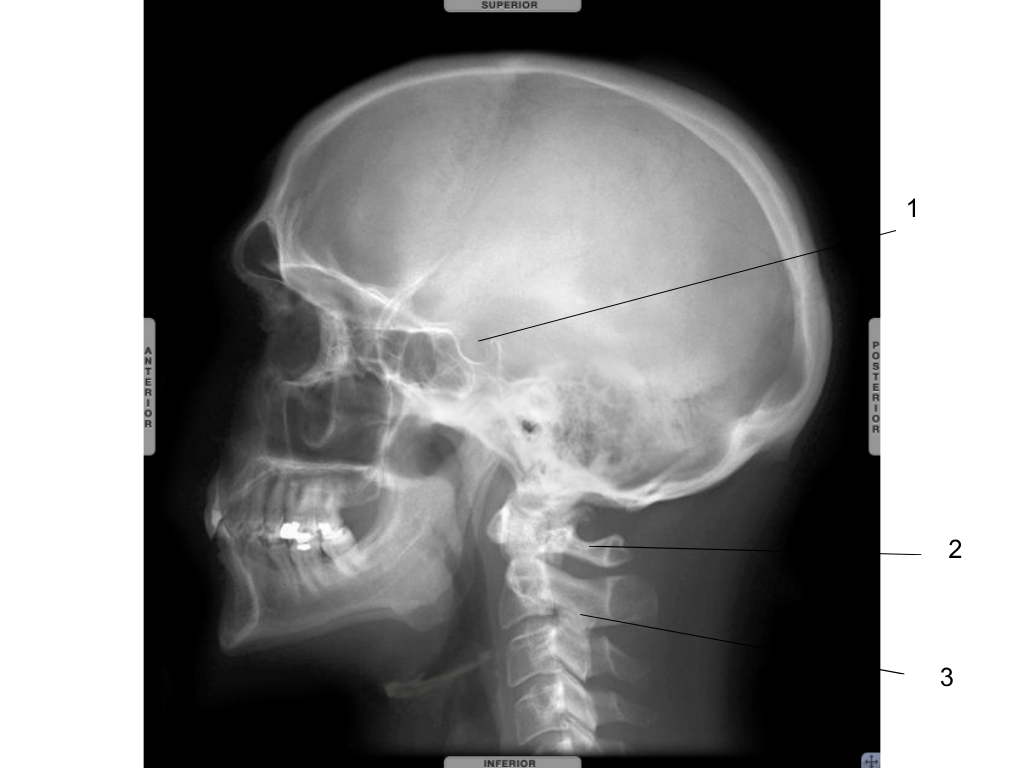

frontal sinus

what is #1 pointing at?

sphenoid sinus

what is #2 pointing at?

sella turcica

Atlas C1

Axis C2

what is #3 pointing at?